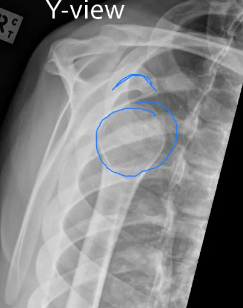

X-ray for: A 20 year old man fell whilst playing football. He had pain and deformity of his right shoulder. He cannot move it.

Does the X-ray confirm your diagnosis? What can you see in the X-rays?

AP view:

Need a 2nd view to confirm: Y-view

What are the 2 blue labels?

Coracoid process and head of humerus (seen here in anterior shoulder dislocation)

What is a Y-view?

The Y-view is taken by aligning the x-ray beams parallel to the plane of the scapula so that it can be seen “floating” over the thoracic wall. In a healthy patient, the humeral head should be in alignment with the glenoid cavity of the scapula.